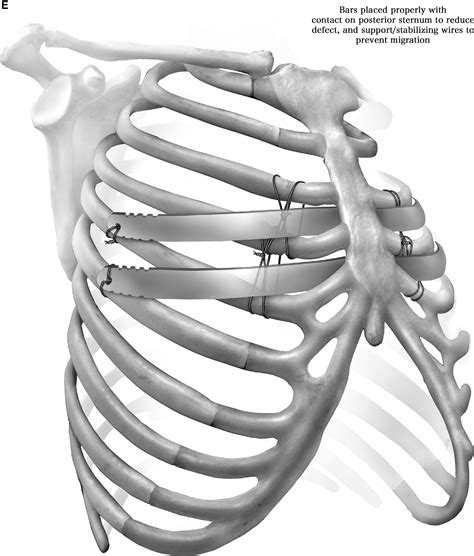

• Incision: A small incision is made on the side of the chest.

• Bar Insertion: A curved metal bar is inserted behind the sternum through the incision.

• Bar Flipping: The bar is then flipped, so the convex side faces the sternum, gradually pushing it outward.

• Closure: The incision is closed with sutures, and the bar is secured in place.

• Bar Displacement: The bar may shift out of position, requiring additional surgery to correct.